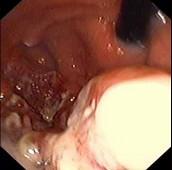

问题 患者,女,19岁,反复发热、上腹痛、消瘦1月,查体:上腹部饱满,余无阳性体征。电子胃镜图片如下,诊断为 ( )

选项 A.胃癌 B.胃淋巴瘤 C.胃溃疡 D.胃溃疡并真菌感染 E.胃多发性息肉

答案 B